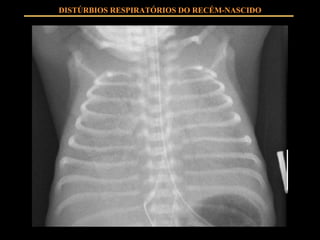

FISIOPATOLOGIA Insuficiente SURFACTANTE produzido por pneumócitos II Instabilidade alveolar com tendência ao colapso em expiração Extravasamento de líquido ao alvéolo Hipoventilação alveolar Shunts intrapulmonares Hipoxemia, hipercapnia DISTÚRBIOS RESPIRATÓRIOS DO RECÉM-NASCIDO